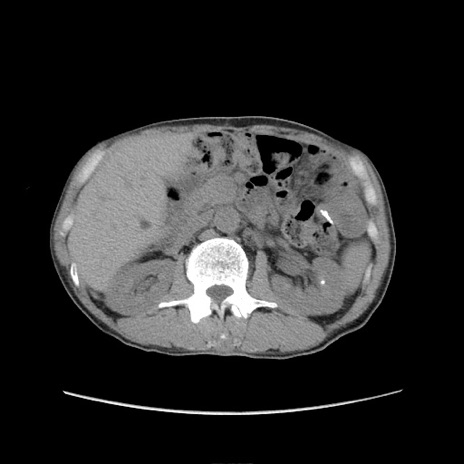

冠状断像

症例11(横断像)

【症例】 60歳代男性

【主訴】 下腹部痛

【現病歴】 本日夜中より下腹部痛の症状認め、受診。

【既往歴】 膀胱癌(膀胱全摘+尿管皮膚瘻術) 、胃癌術後

【身体所見】 BT 35.3℃、PR 58/min、BP 136/98mHg、腹部平坦、軟、腸蠕動音±、ストマ留置あり、左上腹部~正中部に圧痛あり、反跳痛なし。

【データ】WBC 5100、CRP0.01